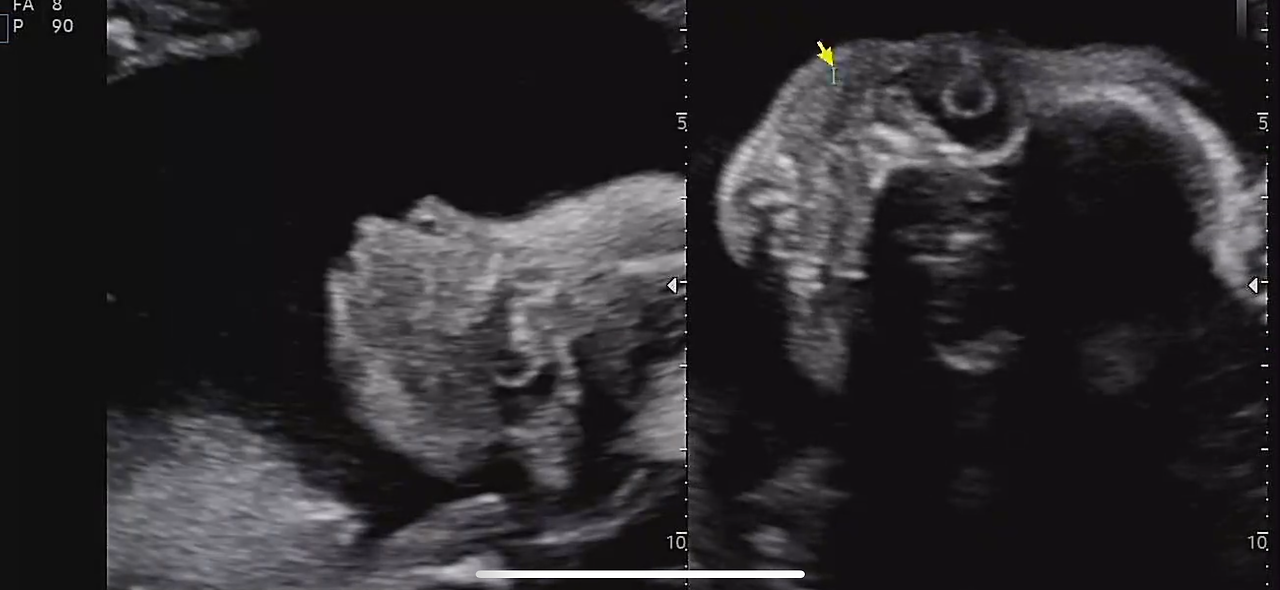

정밀 초음파는 생각보다 오래 걸렸다.

30분 가까이 이어진 검사 동안

손가락, 발가락, 귀, 콧구멍까지

아이는 하나하나 자세히 확인되었다.

22주 정밀초음파

결론은 단순했다.

어떤 부분도 문제없이, 아주 건강하다는 말.